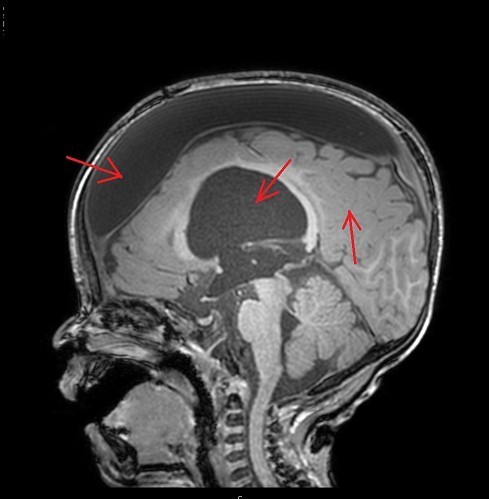

지주막낭종, 평생 모르고 지나가거나, 문제가 되거나...

지주막낭종은 뇌를 둘러싸고 있는 지주막하 공간에 뇌척수액이 들어와 생기는 낭종으로 양성 종양입니다. 지주막낭종은 흔한 뇌종양 중 하나로, 전 인구의 0.1~0.7% 정도에서 발견된다고 합니다. 20~40대에 많고, 남성보다 여성에서 더 흔하게 발생합니다.

1) CT, MRI 촬영 : 지주막낭종의 크기, 모양, 위치를 확인합니다.